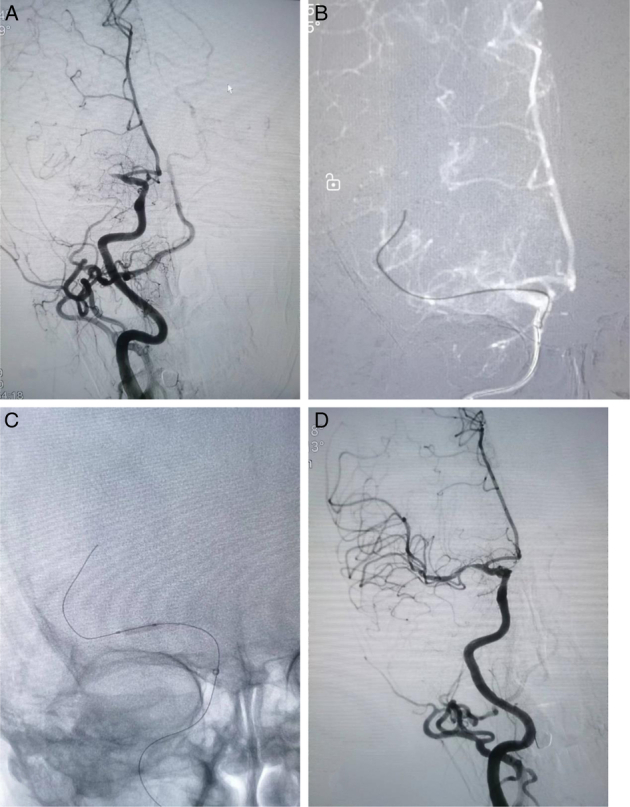

Methods: Data from consecutive EVT patients (May 2020 to September 2023) with acute middle cerebral artery occlusion in ICAS were retrospectively analyzed. Preferred angioplasty was performed if there was a preoperative "microcatheter first-pass effect;" otherwise, preferred stent thrombectomy was performed. Analyses were grouped according to the two EVT treatments. Clinical data of all patients, including the time from puncture to recanalization, rate of successful reperfusion, early neurological improvement, intracranial hemorrhage, and modified Rankin Scale score at 90 days, were recorded and analyzed.

Abstract Image